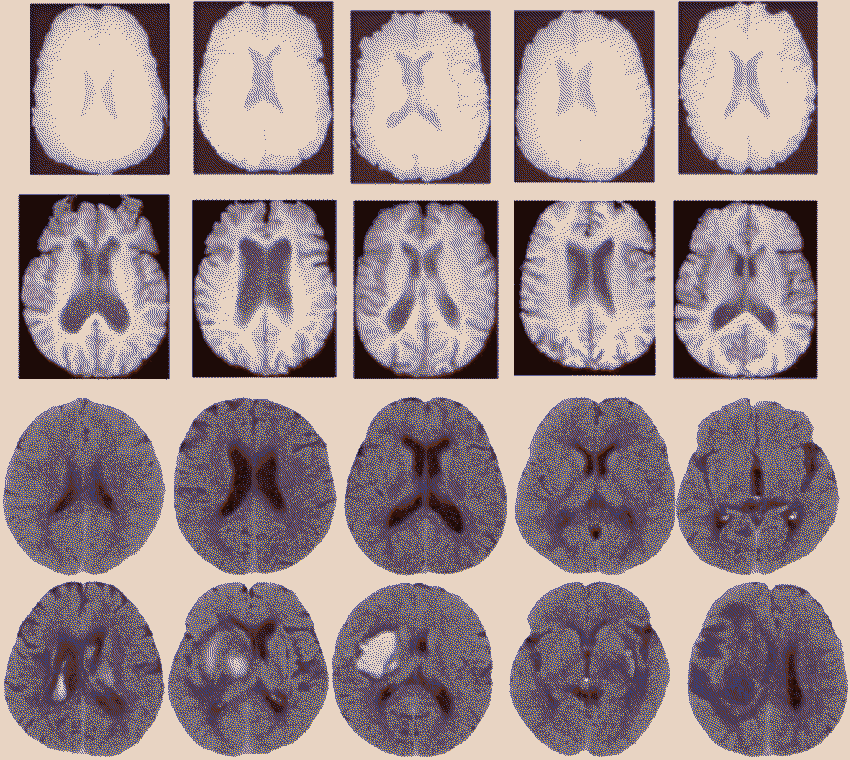

The splenium of the corpus callosum may play a large part in consciousness, and is particularly vulnerable to lesions that may or may not be reversible. In these irreversable cases, patients may be in a vegetative state. However, many powerhouses of the brain may remain unaffected and make up for the body deficit in other ways, similarly to how a blind man may have stronger hearing than a seeing man. Lesions in this area are also linked to seizures, which many psychic events can be mistaken for. The corpus callosum also partially link the right and left hemispheres of the brain, and so issues within this area can cause issues in communication between the two hemipheres.